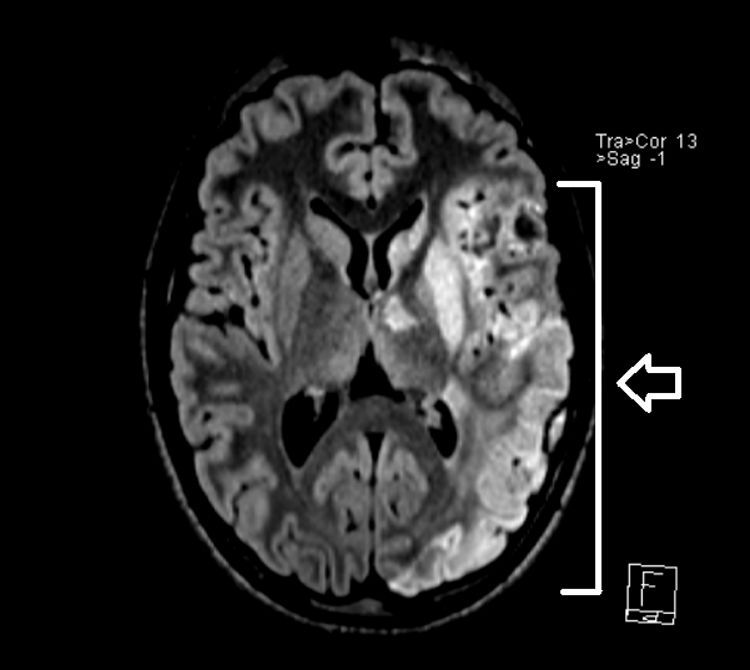

After surgery, the patient started treatment with aspirin (100 mg/day) and underwent structured motor and speech rehabilitation. Follow-up MRI scans (Figs. 2 and 3) showed stable ischemic lesions with no evidence of recurrent embolism. At present, the patient exhibits mild right hemiparesis, nominal aphasia (score of 5 on the PedNIHSS) and slight behavioral changes.